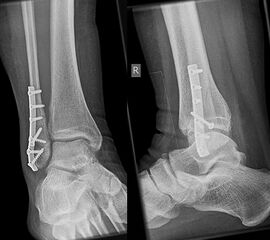

Die Versorgung von AO 44-B Frakturen erfolgt über einen längsverlaufenden lateralen Zugang. In der Regel gelingt eine suffiziente Stabilisierung mittels interfragmentärer Zugschraube (bei langem Frakturverlauf ggf. 2 Zugschrauben) und einer zusätzlichen Neutralisationsplatte (Abbildung 9 & 10).

Bei multifragmentären Frakturen (AO 44-B2.3) oder bei schlechter Knochenqualität sollte die Versorgung mittels winkelstabiler Plattenosteosynthese erwogen werden (Abbildung 11 & 12).

Die Versorgung instabiler Frakturen des medialen Malleolus erfolgt über einen leicht geschwungenen Zugang über den Innenknöchel nach distal verlaufend. Zunächst erfolgt die Exploration des medialen Gelenkanteils und des Frakturspaltes, um eingeschlagenes Periost und Kapselanteile, die eine anatomische Reposition verhindern können, zu entfernen. Anschließend erfolgt die Reposition der Fraktur. Es hat sich bewährt, dies mit einer Spitz-Spitzen-Repositionszange durchzuführen. Dafür erfolgt zunächst eine Bohrung im proximalen Fragment frakturnah um den einen Schenkel der Repositions-Klemme einzuhängen. Der zweite Schenkel wird unterhalb des medialen Malleolus durch das Deltaband eingebracht. Welches Osteosynthese-Verfahren für die Retention der Fraktur gewählt werden sollte, hängt von der Anzahl und Größe der Fragmente, dem Frakturverlauf und der Knochenqualität ab. Bei horizontalem Frakturverlauf und ausreichender Fragmentgröße erfolgt die Fixierung vorzugsweise mittels zweier Zugschrauben (Abbildung 13 & 14). Ist das Fragment zu klein oder handelt es sich um eine mehrfragmentäre Fraktur, so kann die Versorgung wahlweise mit einer Zuggurtungsosteosynthese oder mittels winkelstabiler Hakenplatte erfolgen. Diese Versorgungsarten bieten sich auch bei osteoporotischen Frakturen an.